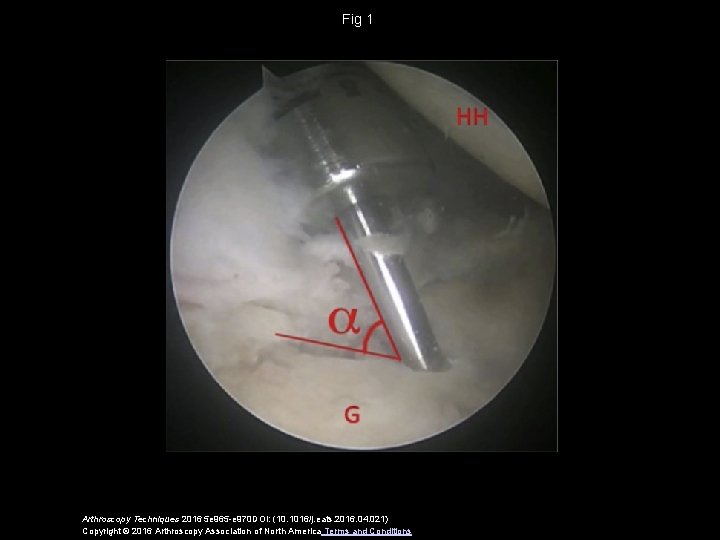

Fig 1 Arthroscopy Techniques 2016 5 e 965 -e 970 DOI: (10. 1016/j. eats. 2016. 04. 021) Copyright © 2016 Arthroscopy Association of North America Terms and Conditions